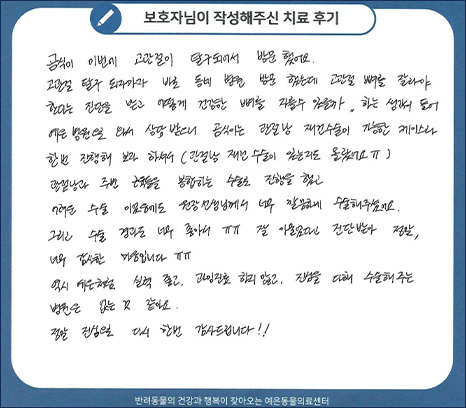

치료 후기 1 관절낭 재건 수술

곰식이 이번에 고관절이 탈구되어 방문했어요.

고관절 탈구 되자마자 바로 동네 병원 방문했는데 고관절 뼈를 잘라야 한다는 진단을 받고

어떻게 건강한 뼈를 자를 수 있을까 하는 생각이 들어 예은 병원으로 와서 상담 받으니

곰식이는 관절낭 재건수술이 가능한 케이스라 한번 진행해 보라 하셔서 (관절낭 재건 수술이 있는지도 몰랐어요)

관절낭과 주변 근육들을 봉합하는 수술로 진행을 했고 어려운 수술이었음에도 원장 선생님께서

너무 깔끔하게 수술해주셨어요. 그리고 수술 경과도 너무 좋아서 잘 아물었다고 진단받아

정말, 너무 감사한 마음입니다. 역시 예은처럼 실력 좋고, 과잉진료 하지 않고 진심을 다해

수술해주는 병원은 없는 것 같아요. 정말 진심으로 다시 한번 감사드립니다!

치료 후기 2 토글핀 수술

갑작스레 고관절이 빠져서 너무 놀랐는데 바로 수술해주시고 아이한테 좋은 방향으로 너무 잘해주셔서

감사해요. 수술 6개월 지나고 완전 정상회복되어 너무 행복하고 감사해요. 우리 아토 다시 걸을 수 있게

장애 없이 수술 너무 감사합니다.